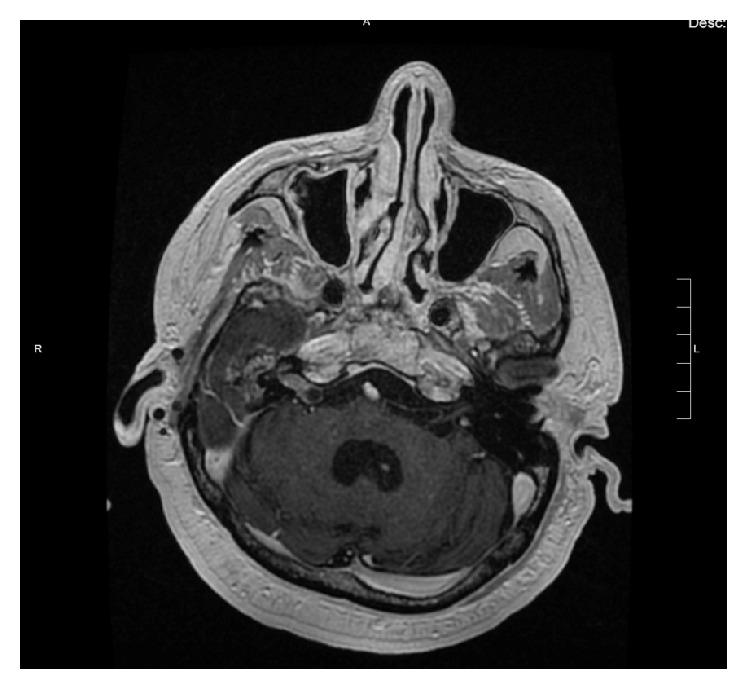

Primary sinonasal and middle ear neuroendocrine carcinomas are rare malignancies of the head and neck. Owing to the rarity of these tumors, the clinical behavior and optimal management of these tumors are not well defined. We present a case of an incidentally discovered sinonasal neuroendocrine carcinoma that was found to originate from the Eustachian tube, which has not previously been described in the literature. This patient was treated with primary surgical resection using a combination of transnasal and transaural approaches and achieved an incomplete resection. Follow-up imaging demonstrated continued tumor growth in the Eustachian tube as well as a new growth in the ipsilateral cerebellopontine angle and findings suspicious of perineural invasion. However, the tumor exhibited a benign growth pattern and despite continued growth the patient did not receive additional treatment and he remains asymptomatic 35 months following his original surgery.